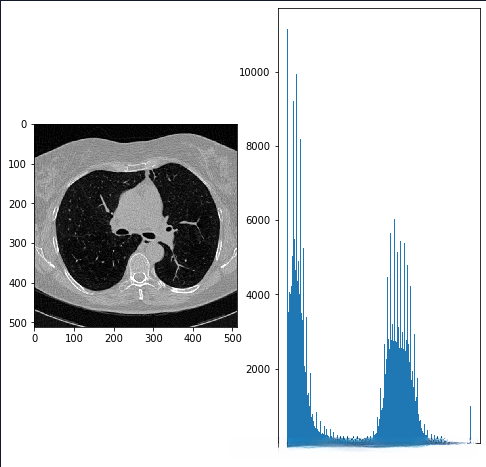

1.标准化数据,查看数值分布:

2.计算位于肺周围区域的平均像素值,并将被遮挡或损坏的图像进行重新归一化处理。通过K-means算法分别识别出目标物体(不透明组织)与背景区域(透明组织),其中背景区域重点关注的是肺部区域。这种处理方法仅针对图像中心区域实施,并尽力避免对未参与区域产生影响